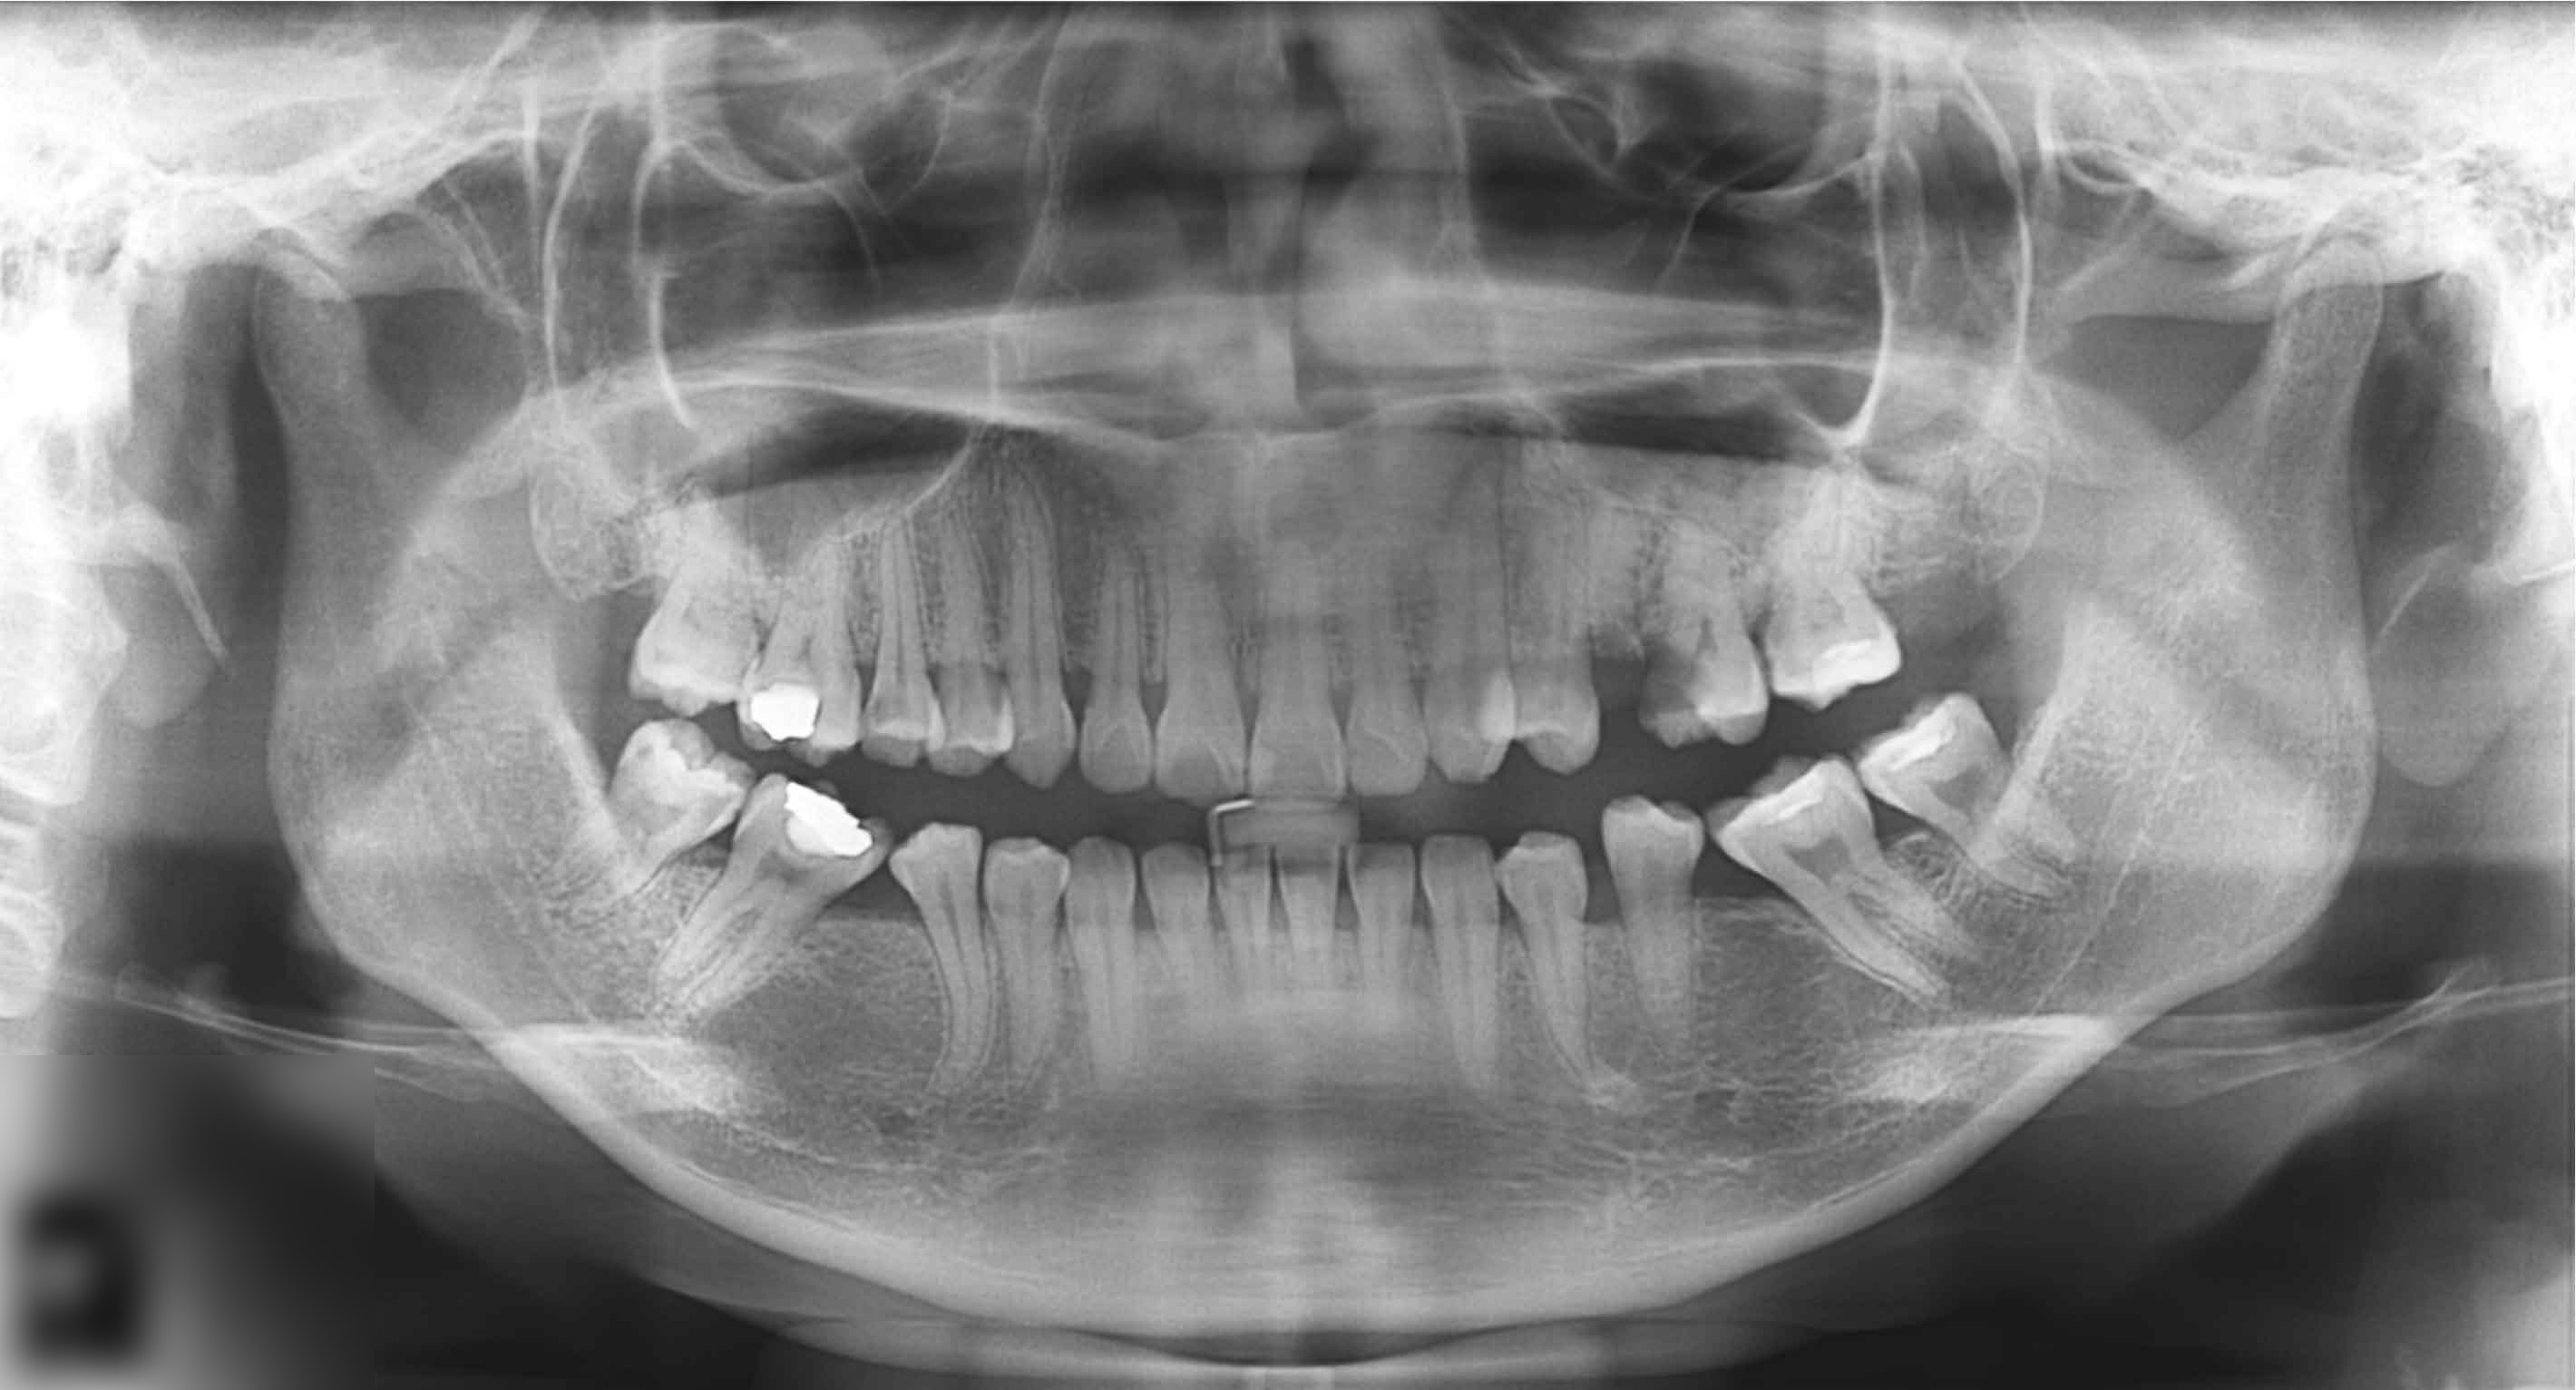

Pacientul Z.A. s-a prezentat la cabinet cu o durere insuportabilă localizată la nivelul maxilarului.